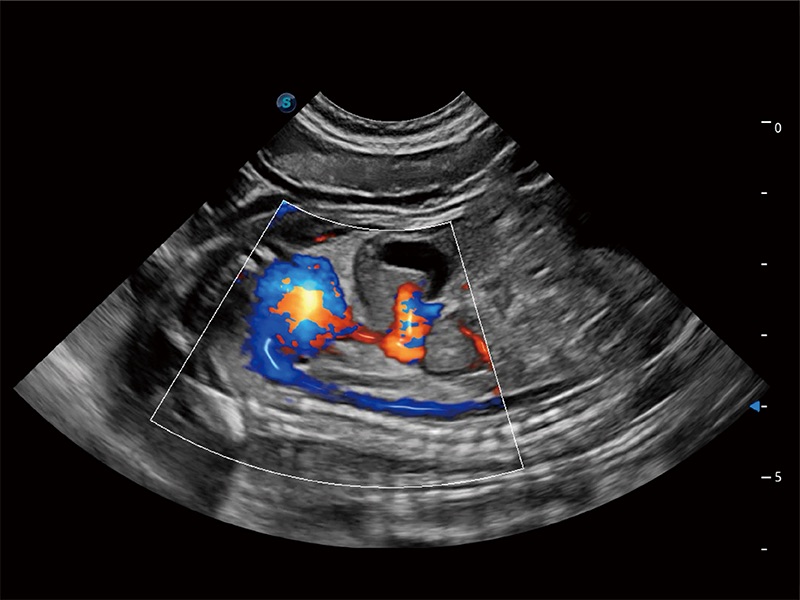

优异的基础图像

ProPet 80 全新的动物超声智能软件和丰富的探头群,为动物医生提供了高清晰度和精细分辨率的图像,无论在宠物、马科、畜牧还是实验室动物等应用中都可以轻松应对,为您的日常工作带来满意的体验。

(犬)四腔心MQA

(犬)肠道